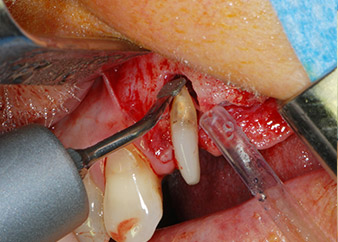

Bone deficiencies around the implants, at the mesial aspect of tooth 27 and around the buccal root of tooth 24, were filled with xenogeneic bone substitute particles and covered with an absorbable collagen membrane (Bio-Gide, Geistlich Biomaterials) for GBR augmentation (Figs. 13 and 14).

Xenogeneic bone substitute material

Fig. 13: Xenogeneic bone substitute material was used to fill the remaining osseous defects …

absorbable collagen membrane

Fig. 14: ... which was then covered with an absorbable collagen membrane. The grayish-pink structure between the elevators at the top margin of the picture represents interproximal papillary tissue.